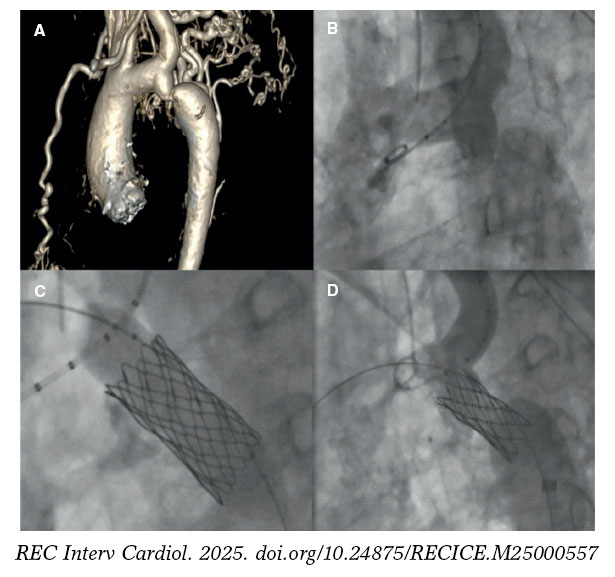

Adequate planning will be crucial in ensuring better outcomes and minimizing the risk of complications associated with coarctation stenting. Several steps may coincide with the BA. The main steps and technical considerations will be addressed below. Figure 2 illustrates a case of an AC successfully treated with stent implantation.

Figure 2. A successful treatment of aortic coarctation in an adult. A: computerized tomography showing aortic coarctation. B: angiography confirming aortic coarctation. C: balloon angioplasty and stent implantation. D: final fluoroscopic result after stent implantation.